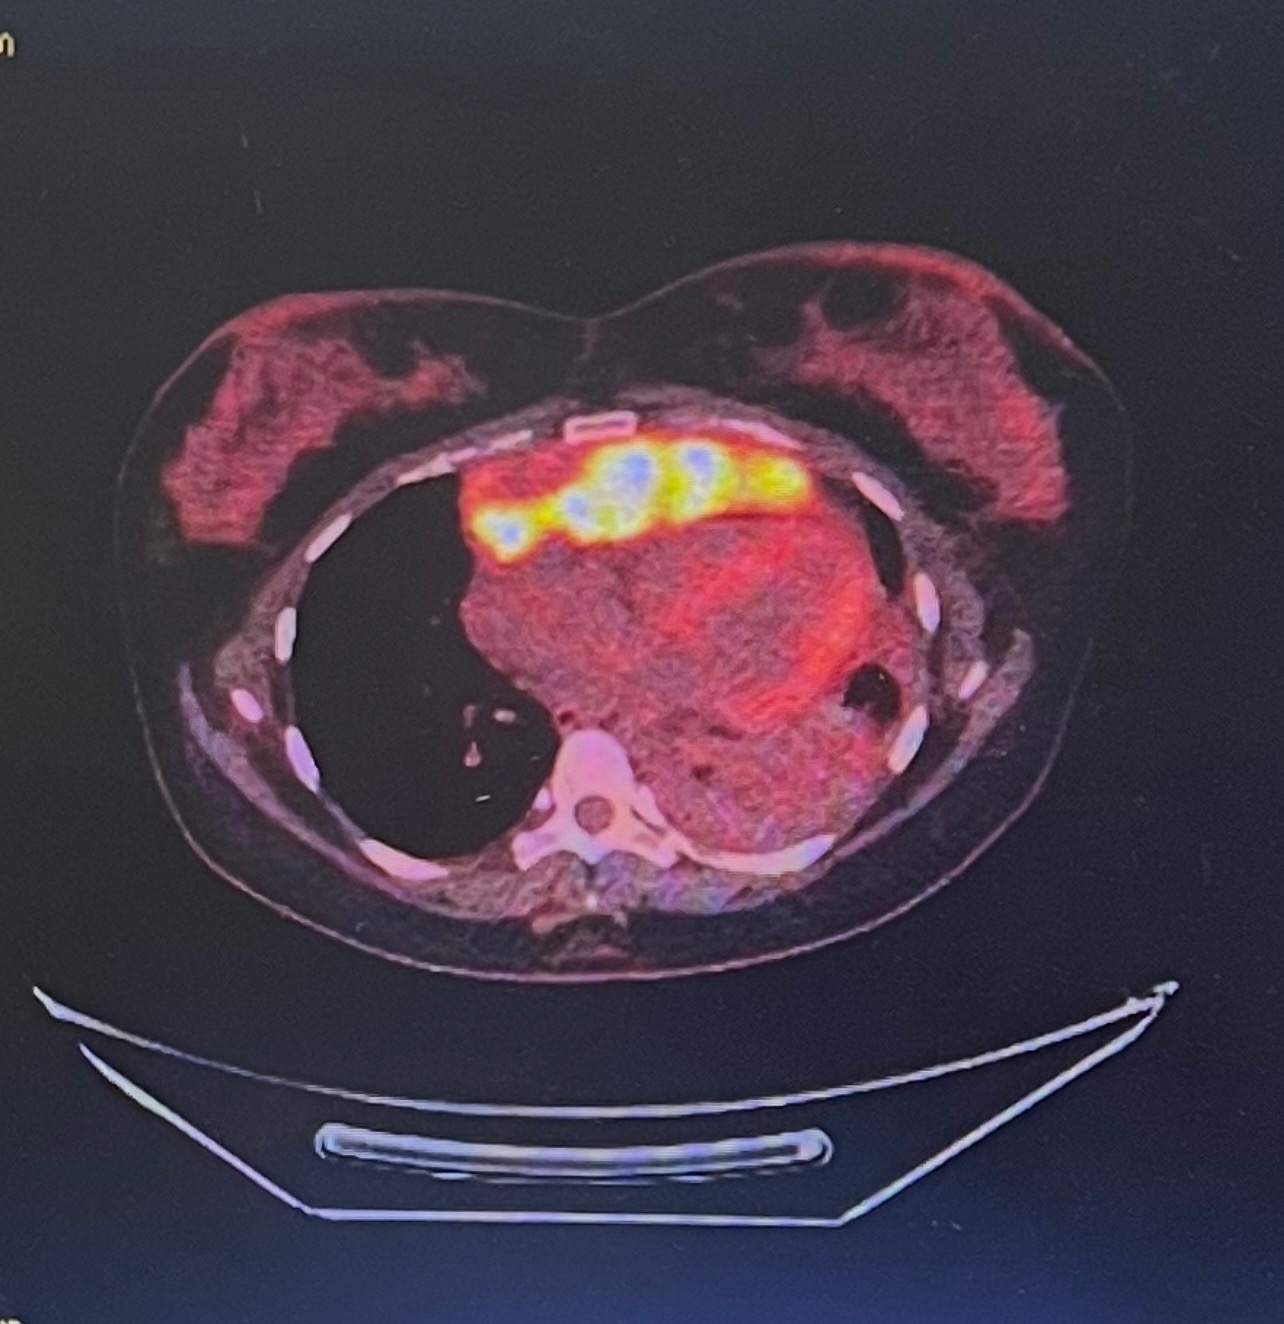

Last summer, my world changed forever. I was pregnant when I was diagnosed with premediastinal B-cell non-Hodgkin’s lymphoma - an aggressive form of cancer. In the midst of what should have been one of the happiest times of my life, I faced the unimaginable: fighting for my life while having to say goodbye to my baby girl, Kainaat Pearl.